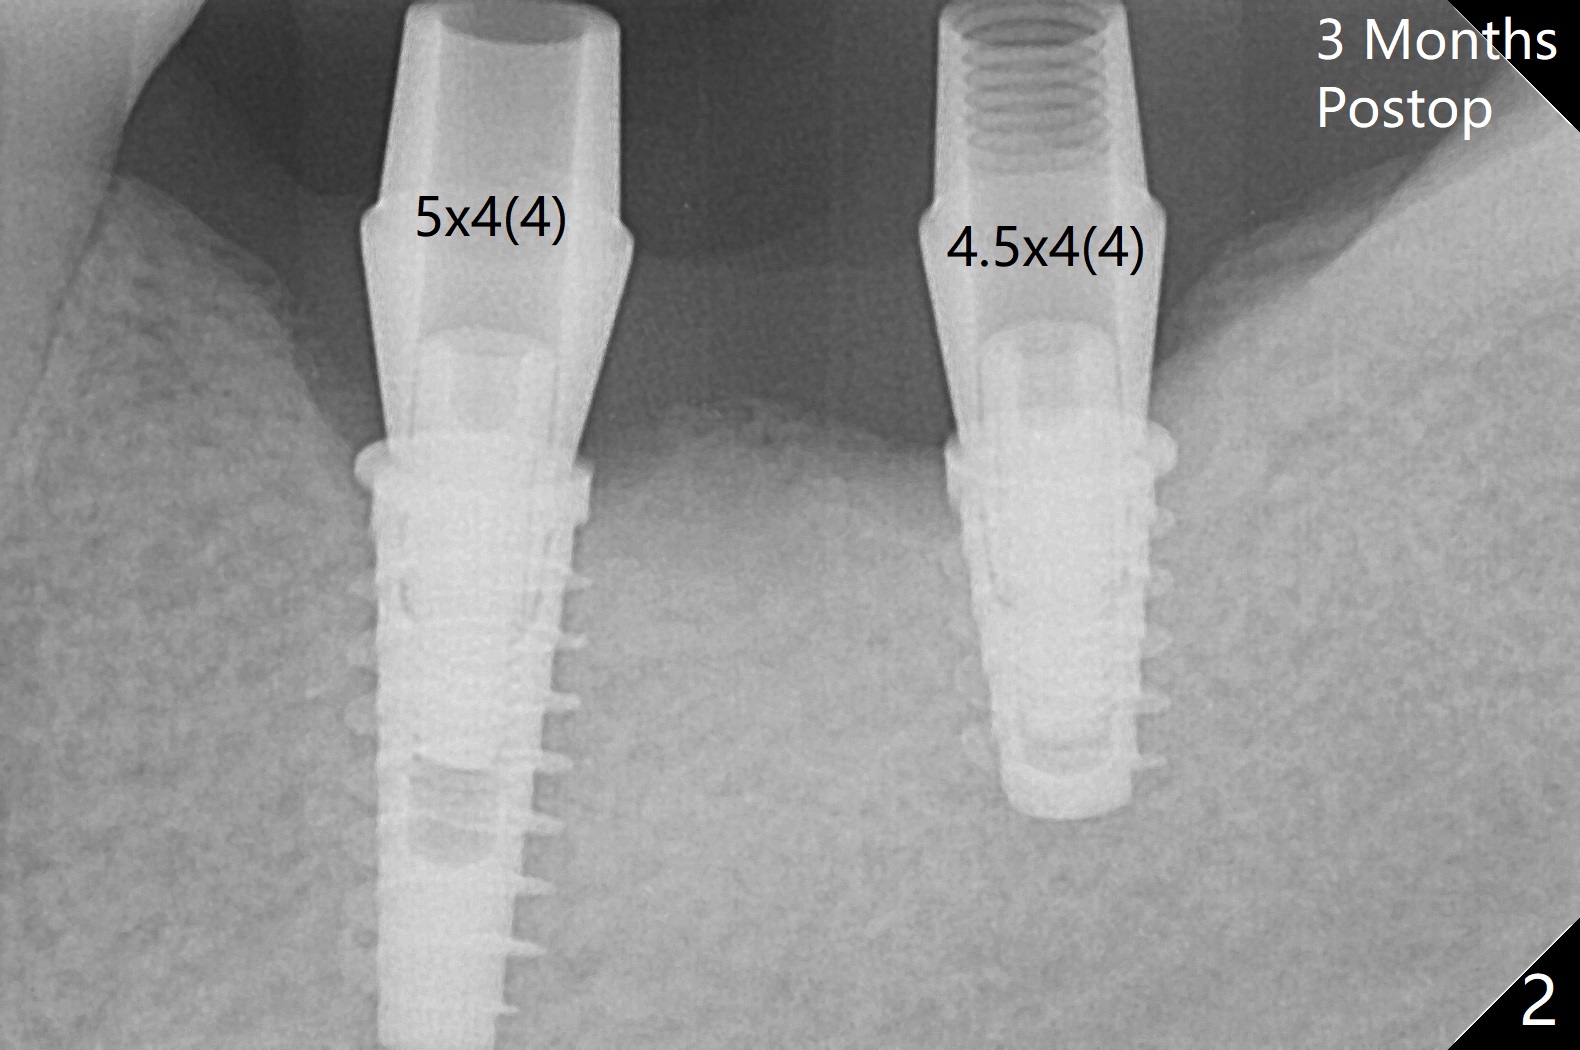

Following placement of a 4.5x11 mm implant at #19 (14 months post guide fabrication), a fixture anchor pin is placed. With stable guide, it is much easier to finish osteotomy and implant placement at #18 (Fig.1). Since the patient is nervous and sensitive to drilling, a shorter implant is placed (7 mm instead of 9 mm vs. 8.5 mm drill). The stability is unaffected because of the dense bone. After use of 5.5 mm profile drill, healing abutments (5.5x3 and 5.5x4 mm) are placed without interference. There is crestal bone loss in 3 months (Fig.2, as compared to Fig.1). Since there is more space apical to the pair abutment at #19 than that at #18, incomplete abutment seating is suspected at #19. More X-ray will be taken (Fig.3,4). In fact, it is not necessary. The space differential is also noted with healing abutments in Fig.1. BW cannot tell whether the abutment at #19 is seated or not (Fig.3). When the abutment is changed at #19 with 30 Ncm torque, the space differential remains (Fig.4, as compared Fig.2) and must be normal. The shorter implant at #18 appears not osteointegrate, since the patient feels pain when the abutment is torqued at 15 Ncm. The patient returns for temporary crown contour adjustment 1-2 weeks later. The implant at #18 is removed when the abutment screw is untightened 7 months postop; Cortical bone is placed with 6 month membrane (Fig.5). Three months later, incision will be made with reuse of the guide with fixture pin at #19. If a 4.5x9 mm implant cannot be placed, bury a short and/or narrow implant. Impression will be taken for #19 soon. In fact fixture pin cannot be seated. It appears that cancellous bone reforms, presumably low density. Underdrilling is conducted in diameter. The torque is high, but normal drilling is not carried out. The former implant exfoliated probably due to compression necrosis. The new implant is not completely seated, partially out of fear of being close to the Inferior Alveolar Canal (Fig.6). After cortical plate perforation, allograft is placed (Fig.7 *), followed by buccal flap release (periosteum underscored). In fact the implant does not have enough clearance from the Canal (red dashed line: the superior border of the Canal). The abutment at #19 returns to hold periodontal dressing in place. The implant is buried in the bone except lingual 4 months postop (Fig.8,9).